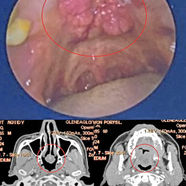

At some point, I understood that I needed more support. I contacted the ECCT team, and they explained to me how ECCT works. During the initial consultation, the team carefully reviewed my medical history, imaging, biopsy results, and symptoms. They encourage me to get proper biopsy and told me that it is likely recurrent of metastatic TNBC. The scan later on does confirm it’s TNBC involving my liver, bone, lung, and lymph nodes. The biopsy as well confirmed a highly aggressive recurrence. The tumour was again triple-negative, now with a Ki-67 of 90%, extensive necrosis, numerous atypical mitoses, and no PD-L1 expression, these features associated with fast growth and limited immunotherapy options.

When I first start for treatment, the tumour was very big. It was visible, and it was painful. My arm movement was restricted. I was very tired, and I had lost weight. Emotionally, it was very difficult for me.

– Breast discomfort from the large, ulcerating tumour

– Night pain